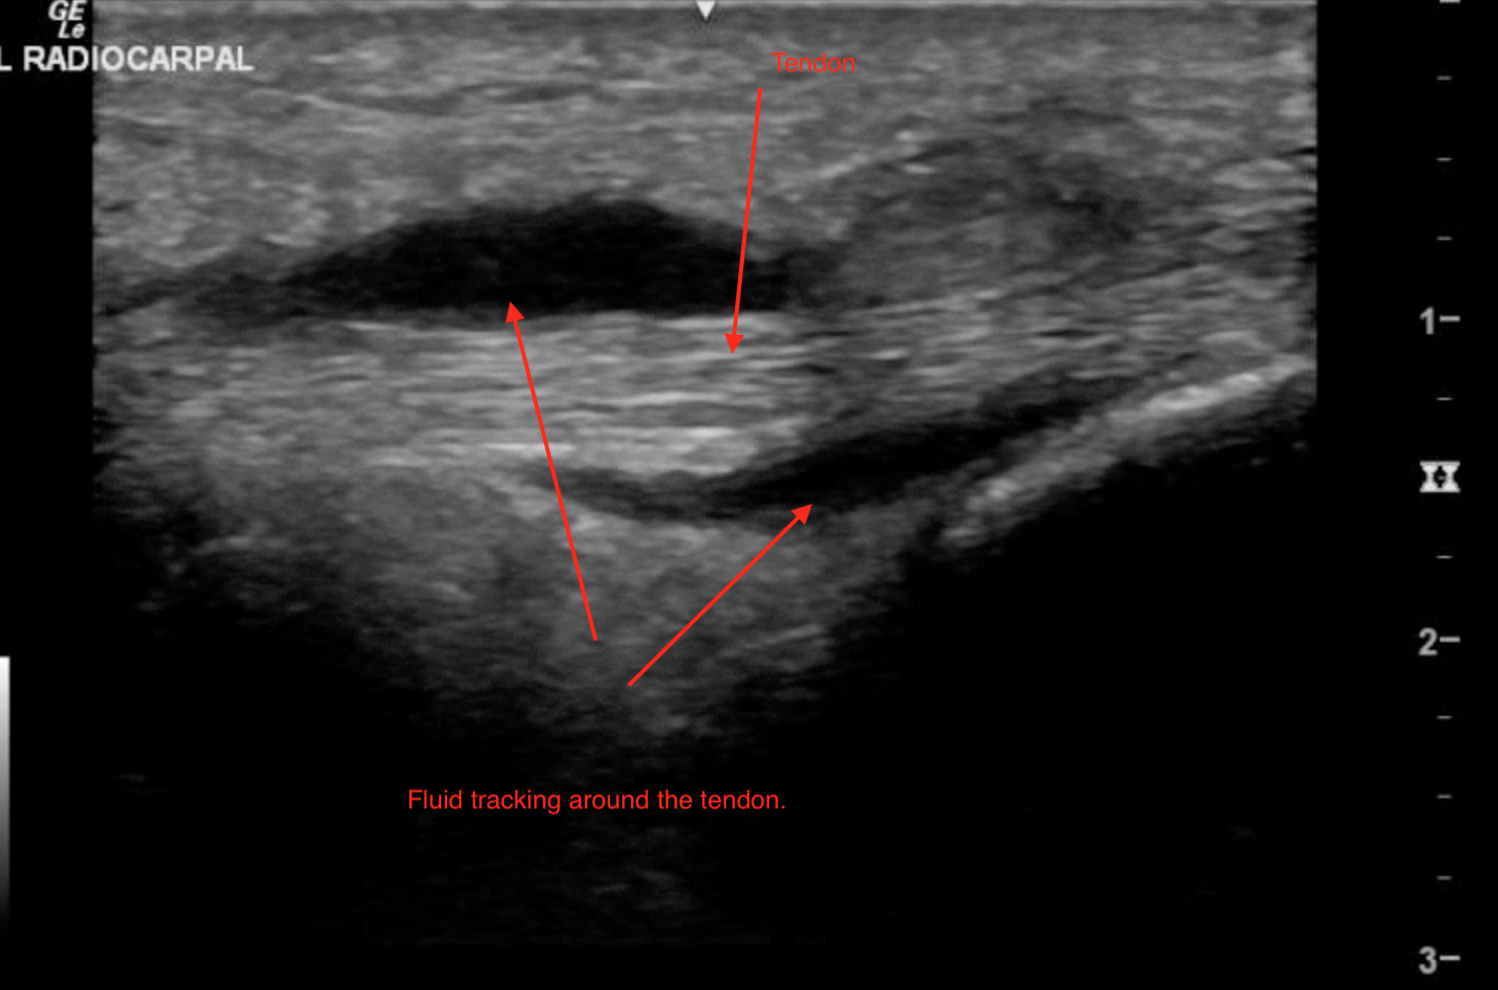

56-year-old male with history of poorly controlled diabetes presents to the emergency room after 3 days of increasing pain, swelling, warmth, and erythema to the dorsum of his wrist. He endorses pain with movement and touching of the wrist.  He denies fevers, but has experienced chills and general malaise.  Ultrasound at the bedside revealed the following images.

This case demonstrates the rare case of extensor tenosynovitis in a middle-aged male with poorly controlled diabetes mellitus. In this example, POCUS provided us the ability to thoroughly assess suspected underlying pathology and visualize the joint space, tendon, and surrounding tissues for inflammation and fluid.  In our images the distorted anatomy of the extensor tendon is clearly visualized, as it is surrounded by abscess and tissue edema. Perhaps more importantly, we can visualize that the joint space itself is intact, ruling out septic arthritis as a possible diagnosis. In this example, a blind attempt at joint aspiration may have led to the seeding of the radialcarpal joint space by the abscess as the needle was advanced through the soft tissues.

Under ultrasound guidance, the abscess was directly visualized and decompressed using a simple needle aspiration technique. The patient experienced immediate pain relief and was promptly admitted to the hospital for antibiotics and orthopedic management.